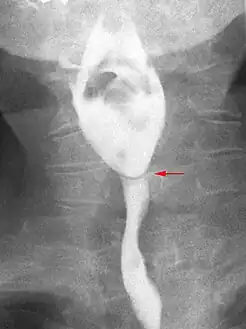

Esophageal webs are thin 2–3 mm (0.08–0.12 in) membranes of normal esophageal tissue consisting of mucosa and submucosa that can partially protrude/obstruct the esophagus. They can be congenital or acquired. Congenital webs commonly appear in the middle and inferior third of the esophagus, and they are more likely to be circumferential with a central or eccentric orifice. Acquired webs are much more common than congenital webs and typically appear in the cervical area (postcricoid).

The diagnostic test of choice is a barium swallow.